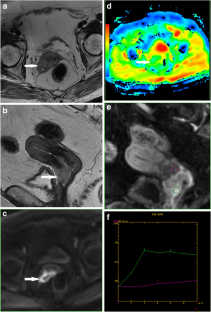

Fig. 1

Fig. 2

Fig. 3

Fig. 4